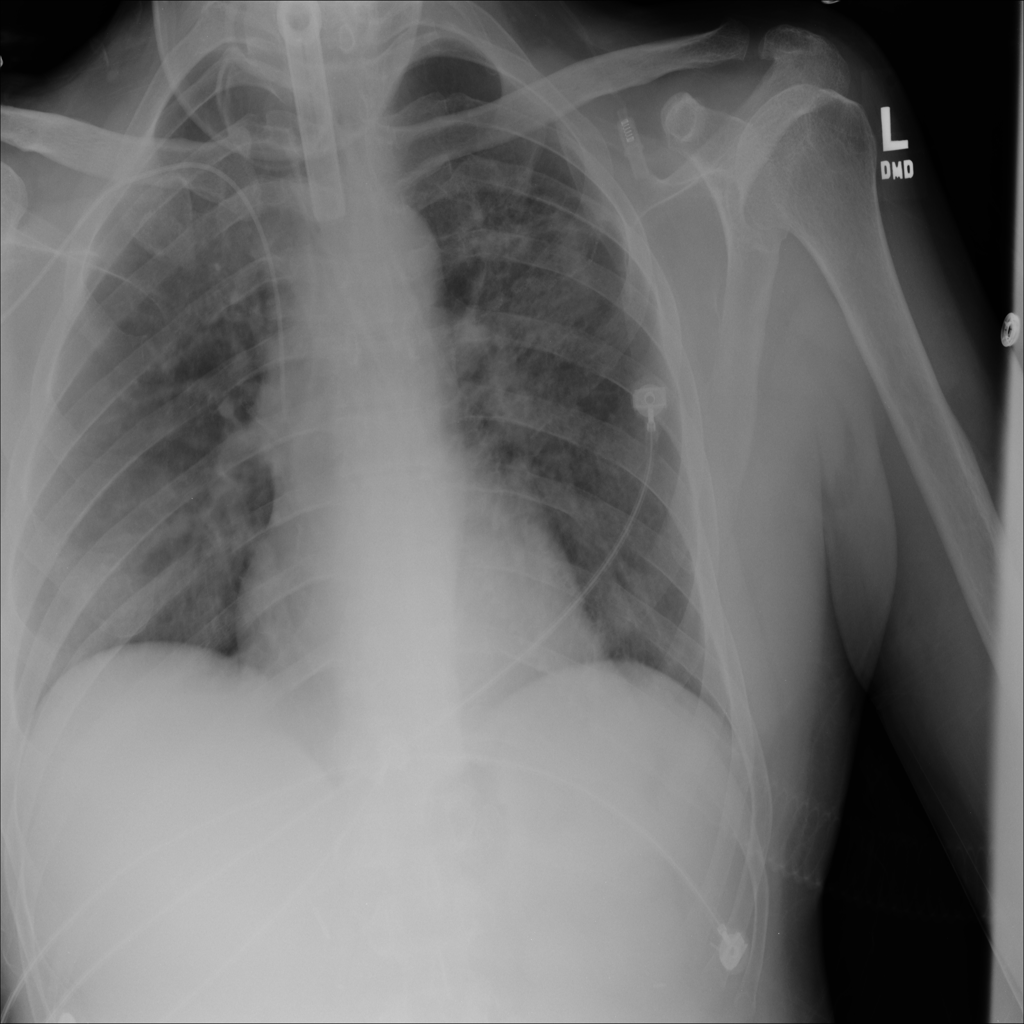

Pneumonia

Pneumonia is an infection of the lung tissue, often caused by bacteria, viruses, or less commonly fungi. On chest X-ray it can appear as focal or patchy air-space opacity, though imaging alone does not always prove the cause.

Showing up to 90 reference images for Pneumonia.

PAT-EBE1 · IMG-019Pneumonia

PAT-EBE1 · IMG-019

AP